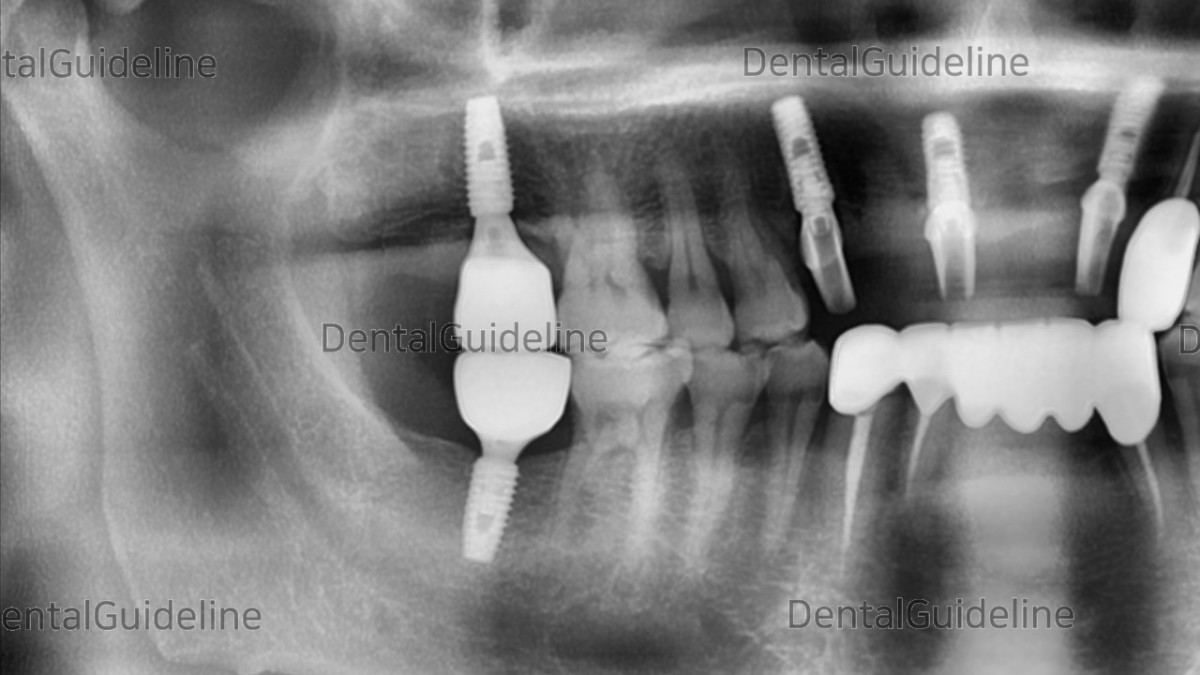

- A panoramic radiograph was taken to verify the secure connection between the scan abutment and the fixture.

-Post-op panoramic radiograph.

- Scan abutments were connected to the implants for digital impression.